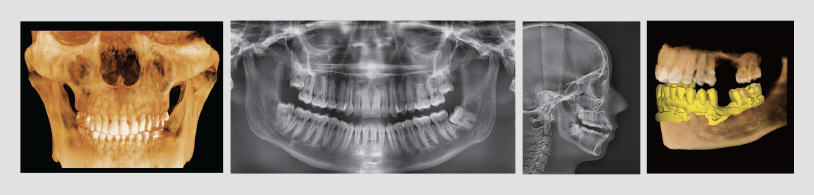

La TC de haz cónico es un tipo especial de TC que se puede utilizar para diagnosticar y realizar exámenes dentales. Una vez capturadas las imágenes, su dentista podrá ver imágenes detalladas de su diente, tejidos blandos, vías nerviosas, huesos y otras estructuras. También pueden mover esta imagen como si tuvieran un modelo tridimensional de sus mandíbulas, dientes y cara. Pueden ver los huesos faciales desde todos los ángulos, incluida la parte superior, posterior, inferior y superior, o cualquier parte de los huesos.

Se llama TC de haz cónico porque utiliza rayos X para tomar las imágenes. El haz de rayos X en forma de cono utilizado para tomar las imágenes tiene la forma de un haz de rayos X. Este haz de rayos X en forma de cono gira alrededor de la cabeza mientras se realiza una exploración CBCT. El extremo ancho del cono apunta a tu cara. La computadora toma de 150 a 200 imágenes de alta resolución, que luego la computadora ensambla en un modelo tridimensional que su dentista puede usar para diagnóstico y examen.

¿Qué Muestra una Tomografía Computarizada de Haz Cónico Dental?

Arverne Dental puede mostrarle los detalles de estas estructuras una vez que se completa una TC de haz cónico dental.

- Los huesos de la mandíbula superior y la mandíbula inferior

- El interior y el exterior de los dientes

- Músculos

- Vasos sanguíneos

- Nervios, canales nerviosos

- Glándulas

- Senos

- Vías respiratorias, incluidas la cavidad nasal y la faringe

- Lengua

- Articulación temporomandibular y cartílago